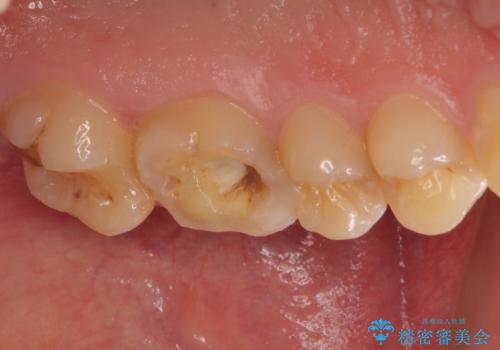

根管治療中の転院 奥歯のオールセラミック治療

- ラバーダムや顕微鏡を用いた根管治療を希望されて、転院された患者様です。

前医にて神経を取り除いた処置を行った際、ラバーダムが使用されなかったとのことで転院されてきました。

根管治療を実施した後、フルジルコニアクラウンに補綴することとしました。